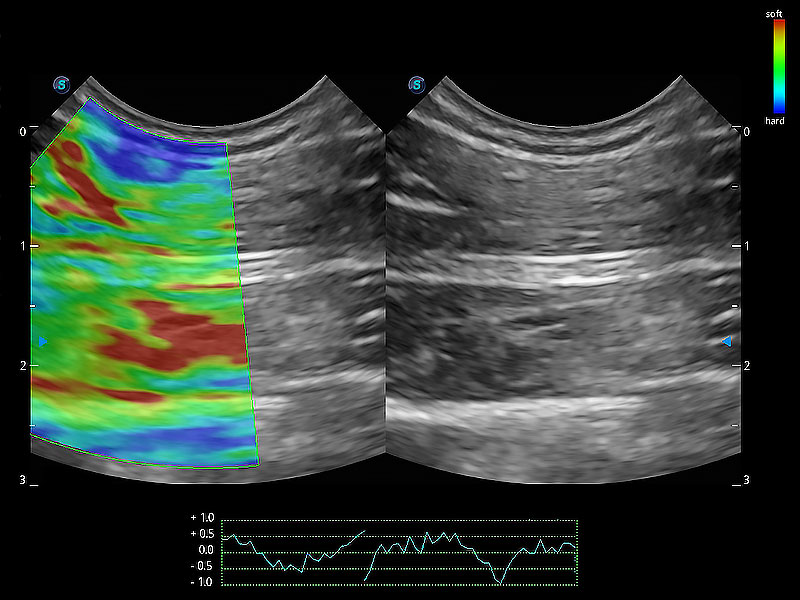

• 应变式弹性成像

操作简便,无需高频度外力作用即可真实反映组织的形变,快速评估肿瘤良恶性。

(犬)肾脏显微血流